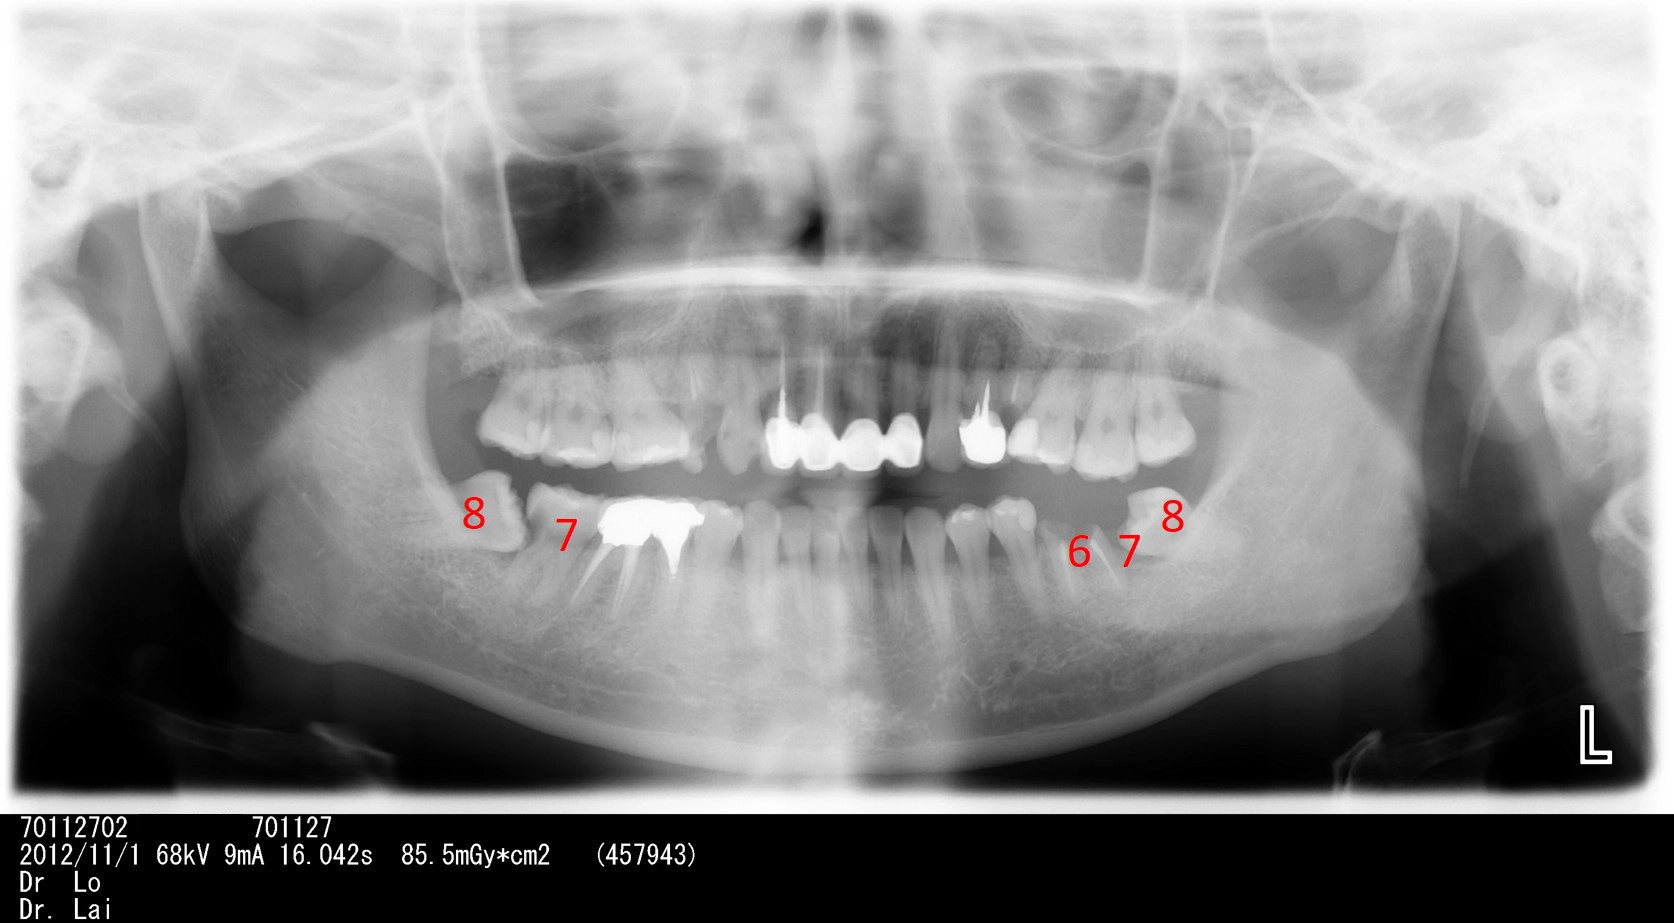

左右下牙兩顆智齒不聽醫師建議拔除,5年後,智齒前面大牙也因智齒而蛀牙,最後拔除4顆牙